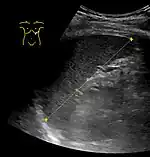

CT scan in a patient with chronic lymphocytic leukemia, showing splenomegaly. Yellow arrows point at the spleen. | |